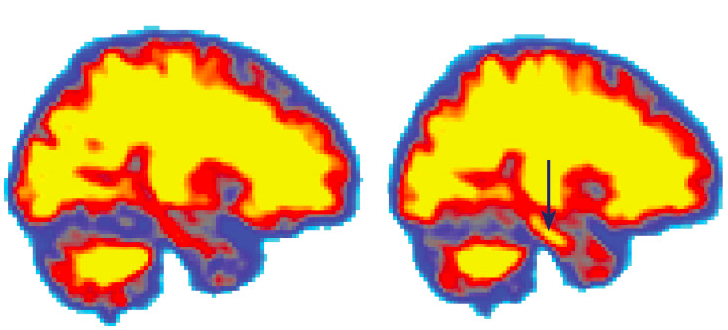

Levels of A-beta rose in a volunteer’s brain after sleep deprivation, shown by the arrow.

Amyloid beta is a protein that is generated as waste by neurons. Higher levels of A-beta are found in people suffering from Alzheimer’s. The body generally cleans up this protein, but this cleaning up process seems to be occurring during sleep. Thus, lack of sleep means inefficient cleaning up of A-beta, which eventually could lead to its accumulation in the brain’s pathways, causing Alzheimer’s.